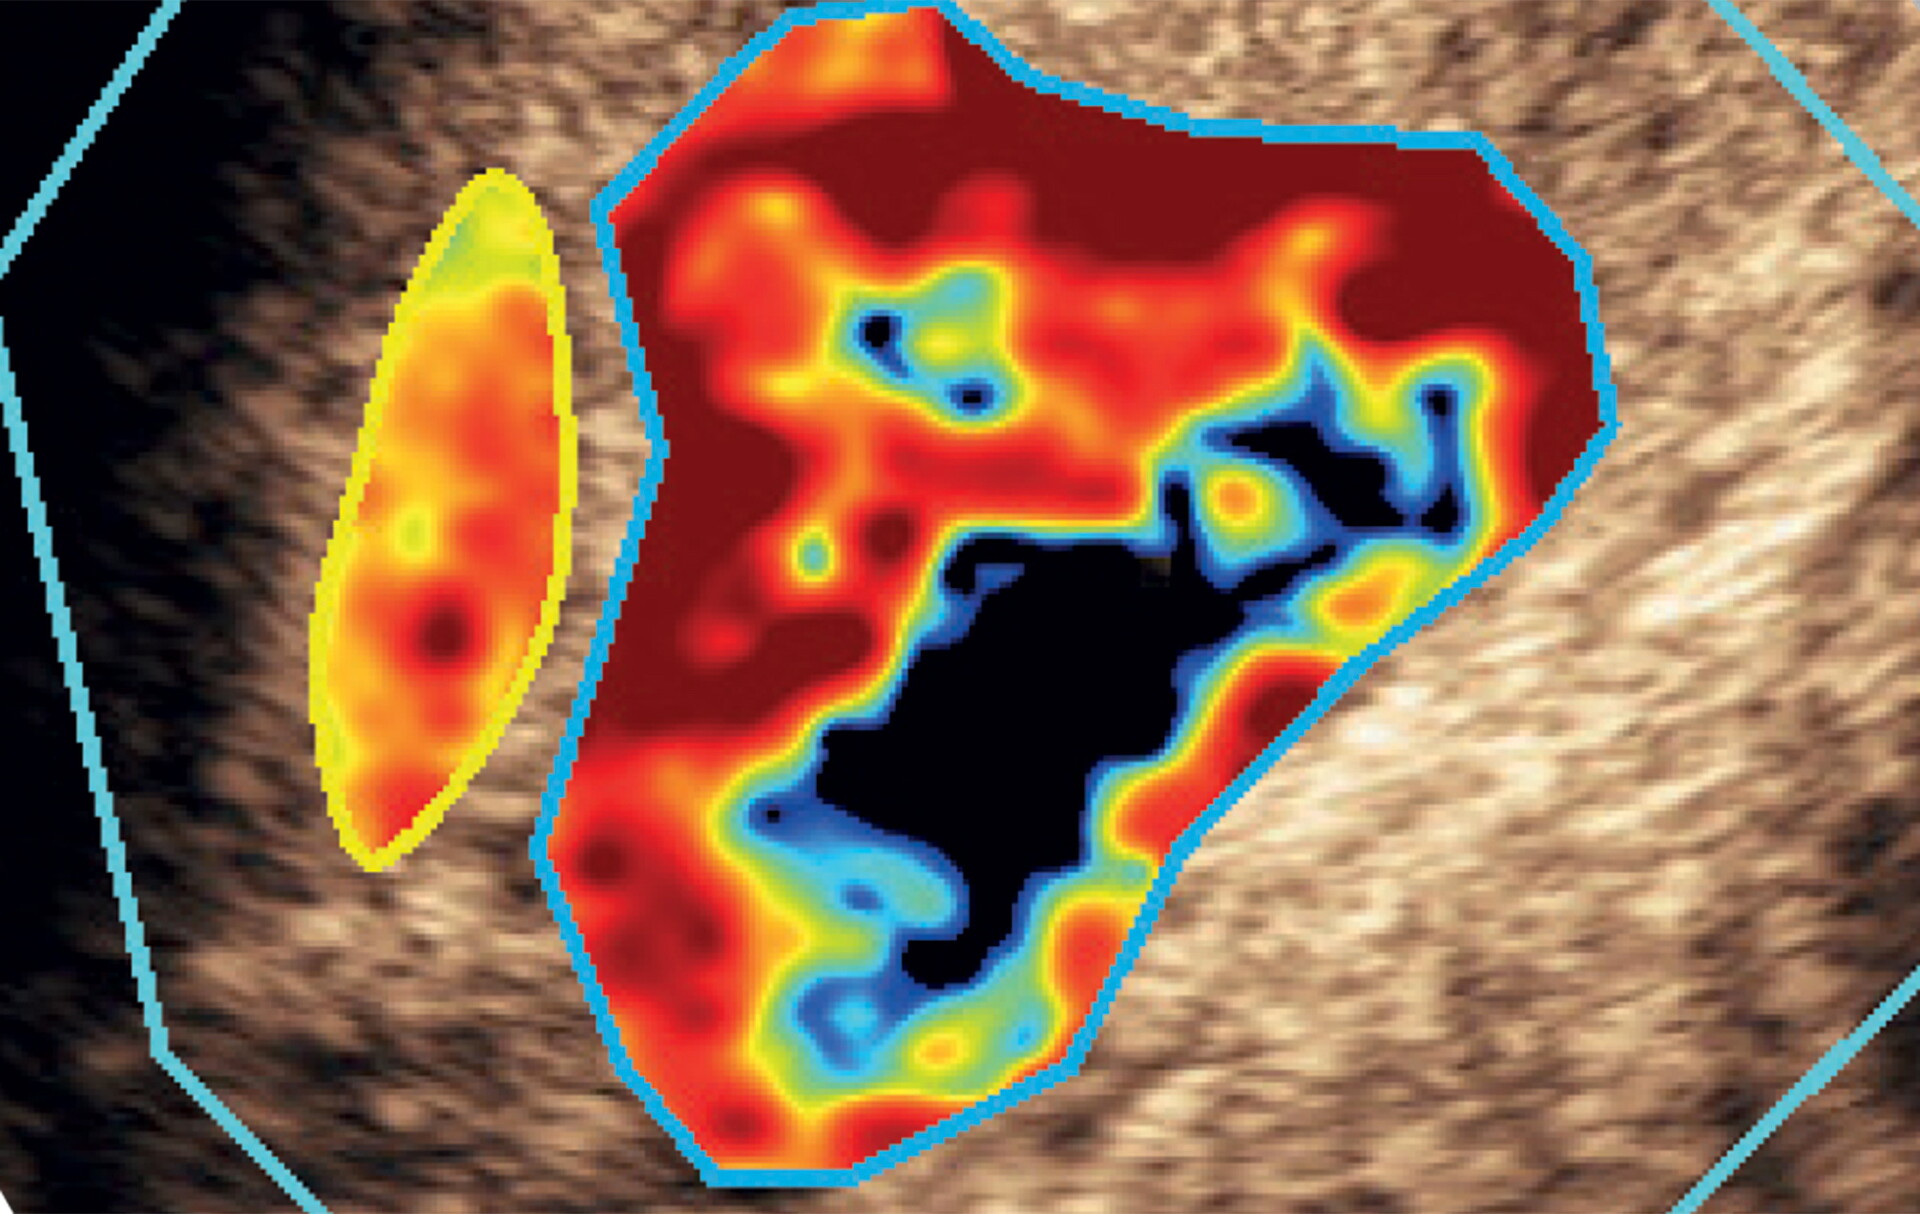

Quantification of blood volume and flow is crucial for determining areas of different perfusion in whole organs/tissues due to impairment of blood supply or to characterize vascular patterns in different tissues and functional aspects of vascular physiology.

Its unique Bracco-patented technology and linearization process allow quantitative assessment of tissue perfusion after bolus injection or infusion.

• Multiple parametric images